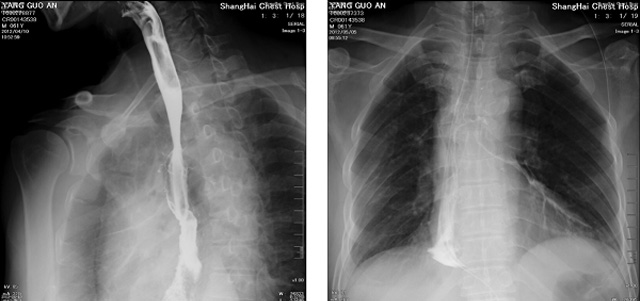

DR設(shè)備在2020年的新冠疫情中,加速了市場調(diào)整。以醫(yī)院為主的向二三級市場轉(zhuǎn)變。特別是小巧靈活的移動(dòng)DR設(shè)計(jì),填補(bǔ)CT和磁共振不能三維檢查的缺點(diǎn),滿足內(nèi)科外科特別是骨科的影像診斷需求。還有懸吊DR設(shè)備CT斷層射線系統(tǒng)。使用錐束成像技術(shù)對整個(gè)脊柱和整個(gè)下肢進(jìn)行了體積三維掃描。無需使用對比劑,即可使用X射線呼吸功能標(biāo)測來模擬模擬氣流和血流,以評估患者的肺動(dòng)脈血栓。

數(shù)字化X線攝影依然是患者初篩的關(guān)鍵一環(huán)。靜態(tài)DR限制于探測器平臺(tái)。只能進(jìn)行簡單普通的數(shù)字化影像檢查。胸部的疾病沒辦法篩查出微小的病灶。這樣導(dǎo)致DR慢慢的被CT跟磁共振代替。這樣造成了原來配套的數(shù)字化影像DR設(shè)備的 閑置。所以DR需要跟CT融合擴(kuò)大DR的檢查使用場景。為DR提高更多的市場價(jià)值。X射線技術(shù)的原始形式和面向未來的可能性打破了CT成像和DR成像掃描技術(shù)之間的限制。融合成像趨勢更加明顯,多峰成像趨勢發(fā)展更加迅速。